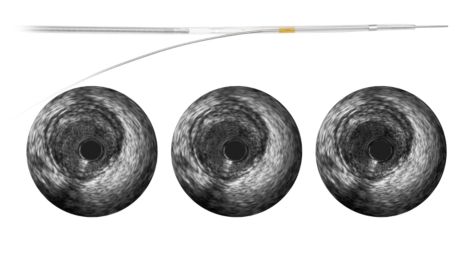

The Revolution rotational IVUS imaging catheter is designed for excellent delivery and imaging accuracy you can trust. It features 45 MHz coronary imaging, high near field resolution, accurate measurements, and excellent deliverability with smooth, sheathed pullback.

A 45 MHz frequency produces crisp, sharp imaging for dependable interpretation and assessment of vessel morphology.